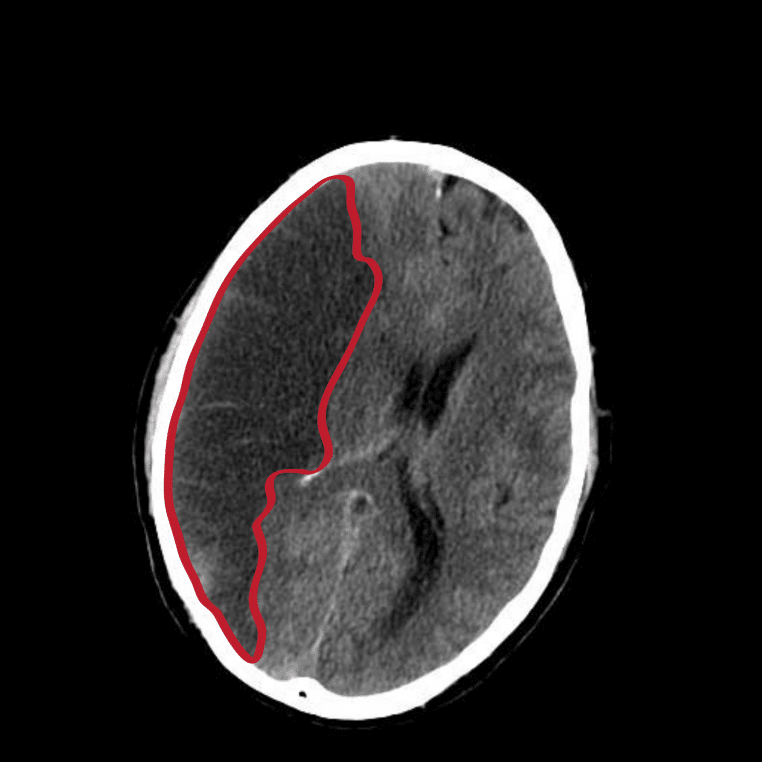

Un AVC silencieux survient lorsqu’un petit vaisseau se bouche ou lorsqu’une microhémorragie affecte une zone limitée du cerveau. La personne ne s’écroule pas, elle ne perd pas forcément connaissance. Ce qui se joue est plus subtil : de minuscules infarctus lacunaires ou des atteintes corticales discrètes qui marquent le tissu cérébral et peuvent, à force de se répéter, altérer la mémoire, l’attention ou l’équilibre. Beaucoup de diagnostics sont faits « par hasard », à l’occasion d’une imagerie demandée pour autre chose.

Ce que l’IRM révèle, parfois bien après

Quand un signe bref évoque un AIT ou un AVC silencieux, la suite doit être structurée. En urgence, l’objectif est d’écarter un AVC en cours et d’identifier la cause probable. Cela passe par un examen clinique, un ECG, une prise de sang et, si besoin, une imagerie rapide. Selon le contexte, une IRM ou un scanner cérébral permet de repérer des lésions passées inaperçues.